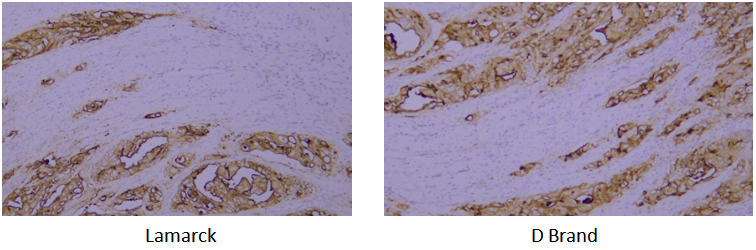

A verification system is established based on the strict requirements of clinical pathological testing. It not only conducts multi-dimensional checks on core indicators of purified antibodies (such as purity, isotype, and IHC performance) to ensure stable and uniform antibody performance, but also verifies via parallel control experiments with well-known international pathological antibody brands. Through horizontal comparison of IHC results on human tissue samples, the detection effect is confirmed to be consistent with and even superior to top international standards.

Target: CK-pan

Tissue: human oral squamous cell carcinoma